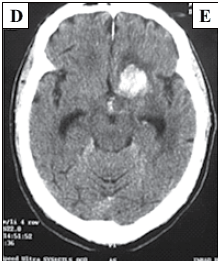

Paciente de 43 anos, hipertenso, apresenta quadro agudo de cefaleia e hemiparesia direita. Exame físico: escala de Glasgow: 14 (sonolento); pressão arterial: 230 x 160 mmHg, pulso: 83 bpm; hemiparesia direita. Tomografia de crânio sem contraste mostrada a seguir.

A conduta correta imediata é